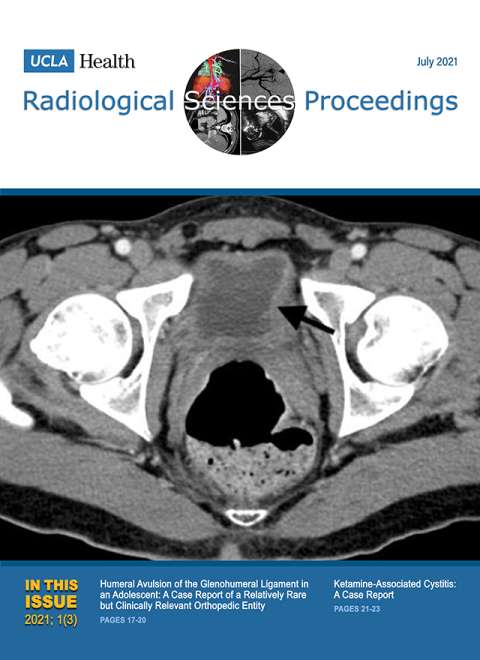

October 2021

Volume 1, Issue 4

- Electronic Integrated Diagnostic Report for Presenting Results of Breast Imaging and Breast Biopsy

- Iatrogenic Axillary Pseudoaneurysm Caused by Ultrasound-guided, Vacuum-assisted Biopsy of the Axillary Lymph Node: A Case Report

- Emergency Intravascular Aortic and Iliac Artery Lithotripsy to Facilitate Thoracic Endovascular Aortic Repair of a Ruptured Thoracic Aortic Aneurysm: A Case Report

- Acute Large Bowel Obstruction due to Pelvic Endometriosis: A Case Report